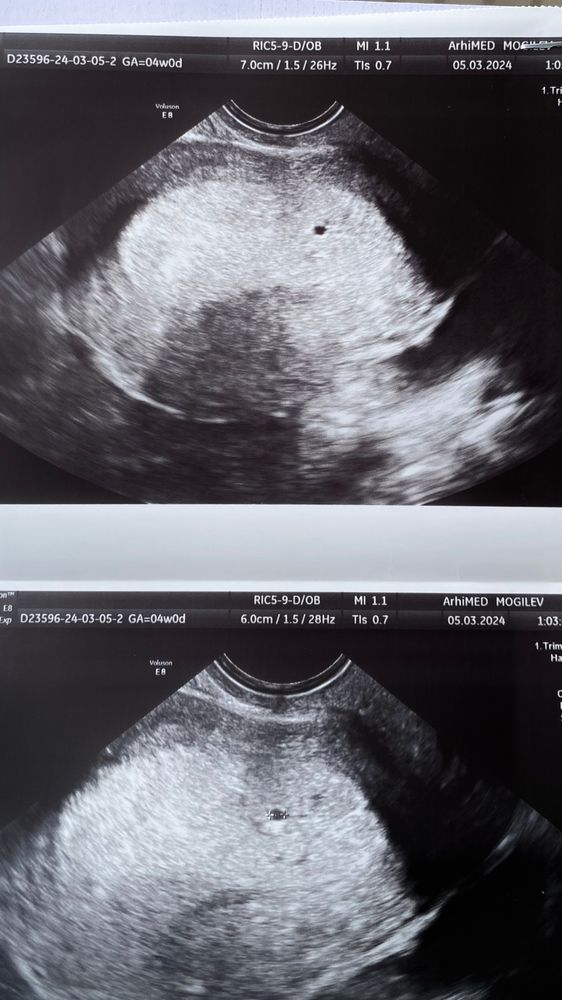

Первое УЗИ 4 недели и 1 день

Это у вас на 13 дпо пя уже увидели? Очень сомнительно,пя 2-3 мм видно при минимальном хгч 750, скорее всего что-то другое нашли,а не пя,его невозможно найти при мизерном хгч,темболие у вас 3 дня назад всего 12 был, сегодня ну максимум 100 может быть при очень быстром росте и пя невозможно увидеть

У меня увидели плодное яйцо с хгч выше 900. И то было очень очень маленькое. Может у вас ошибка в лаборатории была и хгч на самом деле выше? Посмотрите динамику.

Мама мальчика (12 лет)

У вас либо ошибка лабы, либо ошибка узи. С хгч +-12, о котором вы писали 2-3 дня назад, ничего на узи увидеть не могли сегодня